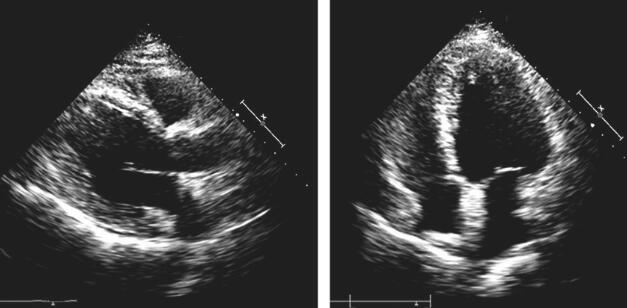

安置心电监护,给予吗啡3mg静推镇静,呋塞米20mg静推利尿,静脉泵入硝普钠控制血压,无创呼吸机辅助通气纠正低氧,给予哌拉西林舒巴坦(3g/次,1次/12h)抗感染治疗。多次复查心电图未见ST-T动态变化,心肌标志物未见明显升高。完善超声心动图(图2):LA 40mm,LV 55mm,IVS 12mm,LVPV 12mm,AAO 32mm,EF 50%;左心稍增大,左室轻度肥厚,左室收缩功能测值稍减低。

图2 超声心动图检查

心力衰竭是多种原因导致心脏结构和/或功能的异常改变,使心室收缩和/或舒张功能发生障碍,从而引起的一组复杂临床综合征,主要表现为呼吸困难、疲乏和液体潴留(肺淤血、体循环淤血及外周水肿)等。根据左心室射血分数(left ventricular ejection fraction,LVEF),心力衰竭分为射血分数降低的心力衰竭(heart failure with reduced ejection fraction,HFrEF,LVEF<40%)、射血分数保留的心力衰竭(heart failure with preserved ejection fraction,HFpEF,LVEF≥50%)及射血分数中间值的心力衰竭(heart failure with mid-range ejection fraction,HFmrEF,LVEF 40%~49%)。该患者存在心力衰竭的症状和体征,超声心动图示左室肥厚,EF 50%,合并BNP升高,并排除了其他引起症状的病因,可诊断射血分数保留的心力衰竭(HFpEF)。